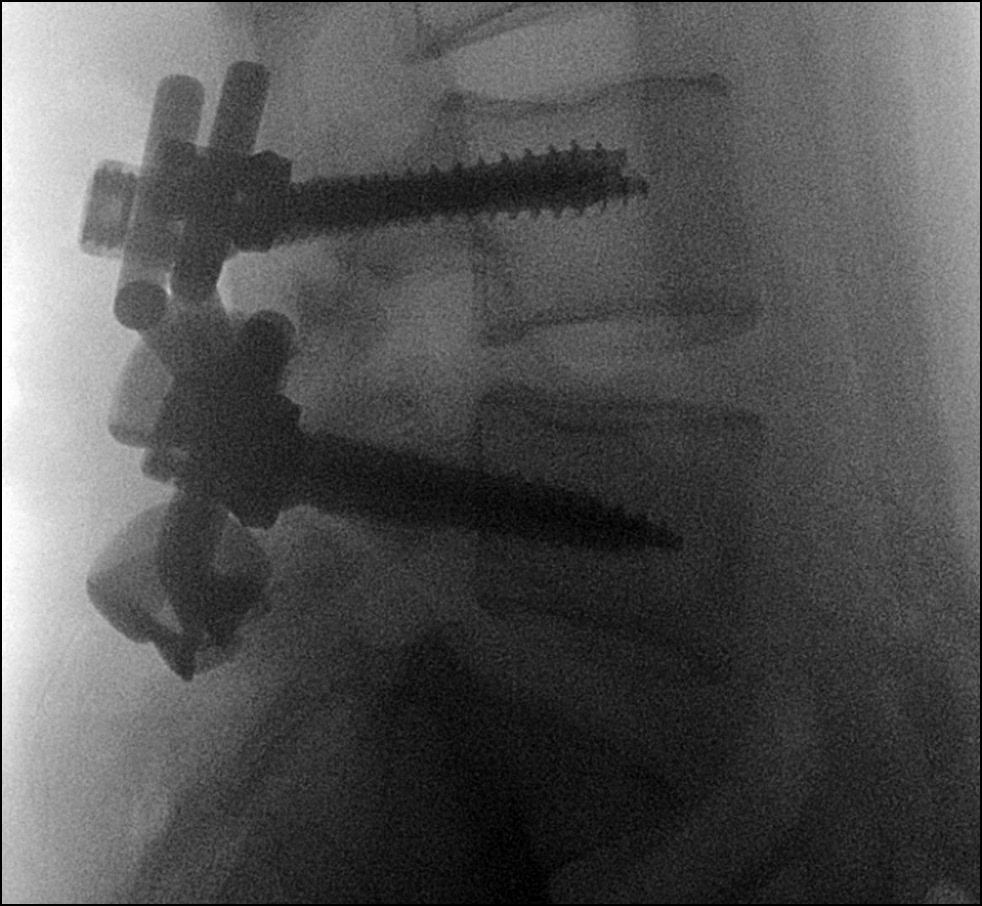

Ход операции: в положении пациента на животе под интубационным наркозом выполнен разрез кожи и подкожно-жировой клетчатки по линии остистых отростков от L4 до S1. Произведено скелетирование дужек L4, L5 позвонков, при этом надостистая связка сохранена. Выполнен гемостаз. Под контролем электронно-оптического преобразователя (ЭОП) произведена установка транспедикулярных винтов через корни дуг в L4 и L5 позвонки с двух сторон с сохранением суставных отростков. С помощью кусачек Керрисона удалена межостистая связка L4-L5, L5-S1. Изогнутым распатором выполнено скелетирование дужек в месте осуществления субламинарной фиксации. Установлена индивидуальная пластина на скелетированную дужку L4 позвонка, причём пластина проведена между остистыми отростками соответственно L4 и L5 позвонков. Аналогичным образом в сформированное отверстие между остистыми отростками L5 и S1 позвонков установлена пластина на скелетированную дужку L5 позвонка. Фиксирующие элементы пластин помещены в головки винтов и фиксированы блокировочными винтами (гайками). Проведён рентген-контроль с использованием ЭОП: положение металлоконструкций корректное (рис. 6). Рана промыта растворами антисептика, послойно ушита. Выполнен внутрикожный косметический шов. Интраоперационная кровопотеря составила 100 мл. Пациент был вертикализирован в первые сутки после операции. Отмечал умеренную боль в области вмешательства, которая регрессировала в течение трёх дней на фоне приёма нестероидных противовоспалительных препаратов. Выполнены контрольное КТ-исследование и постуральная рентгенография позвоночника — подтверждены правильное положение имплантатов и фиксация зоны спондилолиза (рис. 7). На четвёртые сутки после операции пациент выписан из стационара. Рана зажила первичным натяжением.

Рис. 6. Флюороскопический интраоперационный контроль.

Fig. 6. Fluoroscopic intraoperative control.